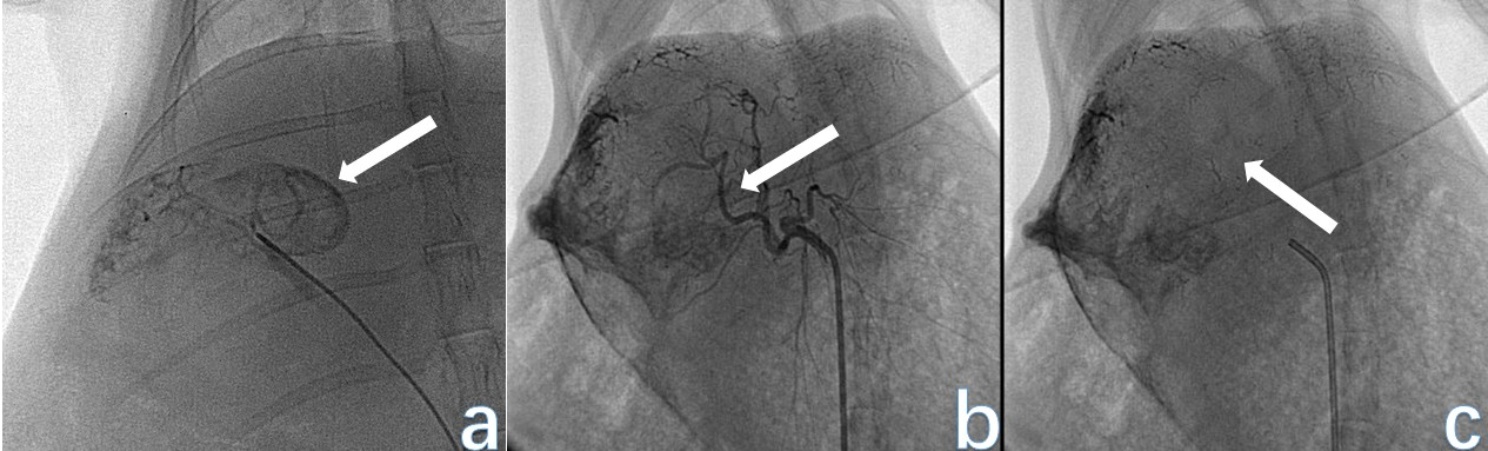

将实验VX2肝癌模型兔全身麻醉后固定在手术台上。备皮、消毒、覆盖右侧腹股沟10 cm以内,做小切口逐层分离皮下软组织,游离股动脉,远端丝线结扎,使用18G穿刺针穿刺股动脉并引入导丝。取出穿刺针后,置入4F导管鞘。4F导管通过导管鞘插入并通过导丝选择进入腹腔干,然后采用同轴导管技术将3F微导管通过4F导管超选择性插入肝总动脉,在DSA引导下确定肿瘤供血动脉。然后,将肿瘤供血动脉插管并通过DSA确认。碘油经3F微导管推入,剂量为厘米数 × 0.2 ml/cm肿瘤直径,根据肿瘤血供适当增减。最后用明胶海绵颗粒栓塞,直至供血动脉血流缓慢停止,行股动脉近端插管结扎处理切口,见图2

(a) 为TAE术中肿瘤供血肝动脉分支较多且走行紊乱,血管推移呈“抱球征”;(b) 为TAE术后复查造影,显示肿瘤供血动脉血流中断,血管闭塞;(c) 为TAE术后平片,见肿瘤区有碘油沉积。

Figure 2. DSA examination of rabbit VX2 liver cancer animal model after TAE surgery

2. 兔VX2肝癌动物模型TAE术后DSA检查